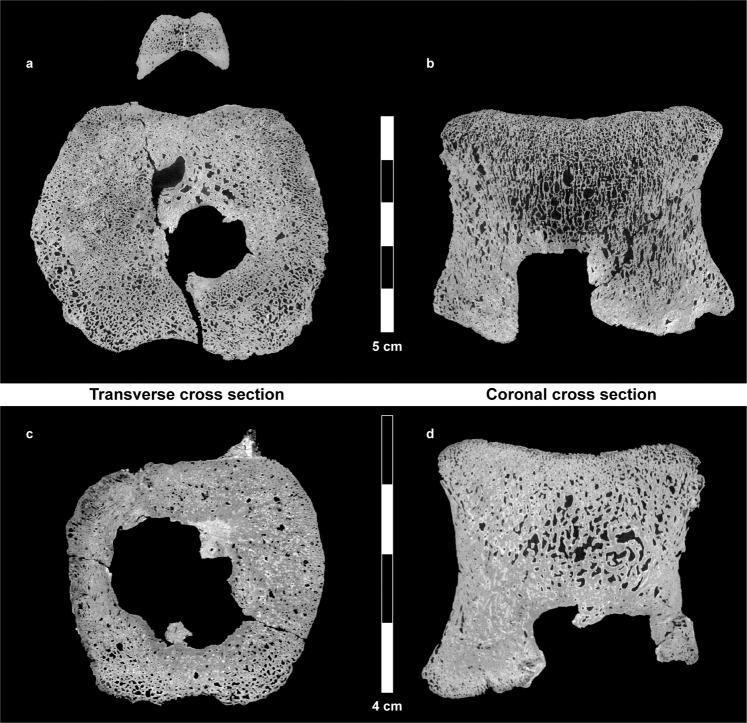

Susceptibility to diseases is common to humans and dinosaurs. Since much of the biological history of every living creature is shaped by its diseases, recognizing them in fossilized bone can furnish us with important information on dinosaurs' physiology and anatomy, as well as on their daily activities and surrounding environment. In the present study, we examined the vertebrae of two humans from skeletal collections with Langerhans Cell Histiocytosis (LCH), a benign osteolytic tumor-like disorder involving mainly the skeleton; they were diagnosed in life, along with two hadrosaur vertebrae with an apparent lesion. Macroscopic and microscopic analyses of the hadrosaur vertebrae were compared to human LCH and to other pathologies observed via an extensive pathological survey of a human skeletal collection, as well as a three-dimensional reconstruction of the lesion and its associated blood vessels from a µCT scan. The hadrosaur pathology findings were indistinguishable from those of humans with LCH, supporting that diagnosis. This report suggests that hadrosaurids had suffered from larger variety of pathologies than previously reported. Furthermore, it seems that LCH may be independent of phylogeny.

疾病易感性是人类和恐龙共有的特征。由于每一种生物的大部分生物学历史都受到其疾病的影响,因此在化石骨骼中识别这些疾病可以为我们提供有关恐龙生理学、解剖学以及它们的日常活动和周围环境的重要信息。在本研究中,我们检查了两个来自骨骼收藏的患有朗格汉斯细胞组织细胞增生症(LCH)的人类的脊椎骨,这是一种良性溶骨性肿瘤样疾病,主要涉及骨骼;他们在生前被诊断出患有这种疾病,同时还检查了两个鸭嘴龙的脊椎骨,这些脊椎骨有明显的病变。对鸭嘴龙脊椎骨的宏观和微观分析与人类的 LCH 以及通过对人类骨骼收藏进行广泛的病理调查以及对来自 µCT 扫描的病变及其相关血管进行三维重建所观察到的其他病变进行了比较。鸭嘴龙的病理学发现与人类 LCH 的发现无法区分,支持这一诊断。本报告表明,鸭嘴龙类患有的各种疾病比以前报道的要多。此外,LCH 似乎与系统发育无关。